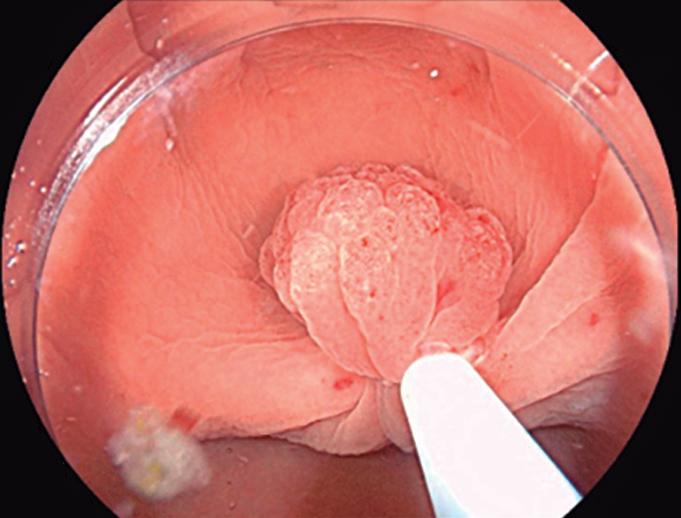

Evaluación endoscópica e histológica

La endoscopía superior es un procedimiento fundamental para el diagnóstico, la evaluación de la respuesta al tratamiento y el monitoreo a largo plazo de la actividad de la EEo. Los hallazgos endoscópicos típicos incluyen edema (reducción de vascularidad), anillos esofágicos fijos, exudados blancos, surcos longitudinales, estenosis, estrechamiento de la luz esofágica, friabilidad de la mucosa (mucosa en papel crepé) y una consistencia firme de la mucosa al realizar biopsias (signo de “tracción" o "resistencia”) en pacientes con fibrosis (Figura 1). Estos hallazgos no son patognomónicos y no constituyen un criterio diagnóstico; sin embargo, cuando se evalúa de forma cuidadosa, en la gran mayoría de los casos se pueden observar.19-21

Un elemento fundamental en la evaluación de la EEo es la aplicación del puntaje de referencia endoscópica para la esofagitis eosinofiílica (EREFS por sus siglas en inglés: Eosinophilic Esophagitis Endoscopic Reference Score).20 El acrónimo EREFS también refleja las cinco características endoscópicas principales de la EEo: Edema, anillos esofágicos (Rings), Exudados, surcos longitudinales (Furrows) y estenosis (Stricture). Estas características se clasifican según su severidad mediante un sistema de puntuación que oscila entre 0 y 9, considerándose la región esofágica con la alteración más marcada. El EREFS cuenta con validación interna y externa, y ha demostrado una elevada capacidad para diferenciar la EEo de otras patologías no relacionadas en poblaciones pediátricas y adultas, además de correlacionarse con la respuesta terapéutica.23-25 Por estos motivos, el EREFS constituye un sistema estandarizado para la evaluación

En el panel A se observa un esófago con edema difuso y pliegues longitudinales; en el panel B se aprecia edema con pliegues y exudados blanquecinos; en el panel C se evidencia un estrechamiento luminal acompañado de anillos esofágicos y exudados; y en el panel D se muestra un desgarro mucoso posterior a la dilatación con bujía de Savary, hallazgo esperado tras este procedimiento terapéutico.

Figura 1. Características endoscópicas de la esofagitis eosinofílica